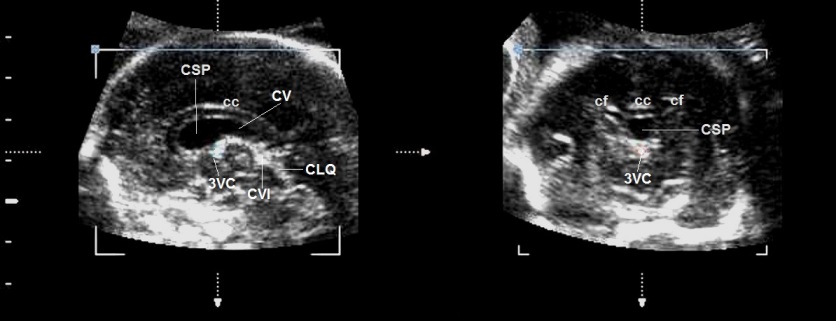

Il Cavum Vergae ed il Velum Interpositum sono strutture normali dell'encefalo fetale il cui riconoscimento ecografico deve partire dalla corretta visualizzazione del cosiddetto complesso cavo del setto pellucido/cavum Vergae. Il cavo del setto pellucido è una fessura mediana tra le due lamine del setto pellucido. Il Cavum Vergae (descritto dall'anatomista italiano Andrea Verga ) è l'estensione posteriore del cavo del setto pellucido. La reale linea di divisione tra CSP e CV è il fornice, ma dal momento che quest'ultimo non è facilmente visibile ecograficamente, sul piano mediosagittale è possibile utilizzare il forame di Monroe per demarcare il limite tra i due cavi.

Sul piano mediosagittale il complesso CSP/CV è

delimitato in alto dal corpo calloso e in basso dalla corioide che riveste il

tetto del terzo ventricolo. Ed è proprio la corioide del terzo ventricolo a

fungere da marker per il riconoscimento del limite tra i due cavi. Infatti il

limite anteriore della corioide corrisponde topograficamente al forame di

Monroe ed è questo punto che rappresenta il confine tra cavo del setto

pellucido e cavum vergae: il cavo del setto pellucido termina nel punto in cui

inizia la corioide del terzo ventricolo e da questo punto in poi comincia il

Cavum Vergae.

Sul piano coronale Il complesso cavo del setto pellucido/cavum

vergae è delimitato lateralmente dai corni frontali dei ventricoli cerebrali

laterali e superiormente dal corpo calloso.

Cavum Vergae

Il cavo del

verga (cavum vergae) è l'estensione posteriore del cavo del setto pellucido nel

periodo fetale; lo si reperta al disotto dello splenio del corpo

calloso e in un 30% dei casi lo si può visualizzare anche nel periodo

neonatale.